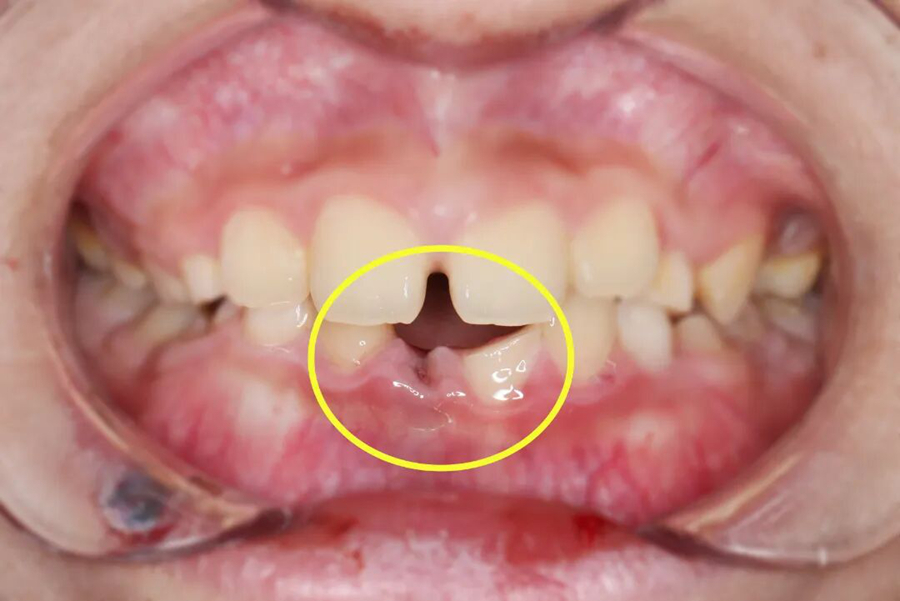

“牙齿脱落时间越久,再植成功率越低,每一分钟都很关键!”口腔中心接诊后,立刻启动急救模式。口内检查和拍片检查发现,小千脱落的牙齿牙根完整,折断的牙齿已露髓(可见红点出血)。

第一步,牙齿再植

救治团队小心翼翼地接过家长带来的脱落牙齿,用专业工具轻柔清理牙根表面的污染物,确保不损伤牙根组织,随后精准将牙齿植入原来的牙槽窝,再用特制纤维带将其与相邻健康牙齿紧密结扎固定,为牙齿重新愈合提供稳定支撑,整个再植过程一气呵成。